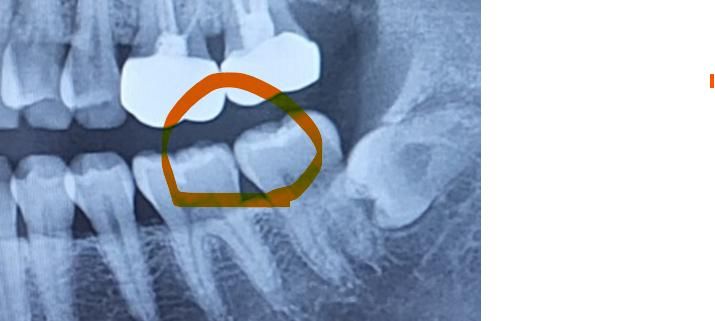

왼쪽 아랫니 부분인데 지금 치과를 2군데 다녀왔는데 어떤 곳은 이상이 없다고 하고 어떤곳은 치아 양쪽이 충치라 인레이 ㄱ모양으로 하고 그 옆은 레진으로 해야한다고 해서 누구말을 믿어야하나요..?

• 2번 째 사진

정확한건 치아 작은 사진을 찍어보시는게 좋을것같습니다. 치아 사이에 충치가 조금 잇어 보이긴합니다.

사진으로 봤을 경우 미세한 음영이 보입니다. 초기 충치일수 있으며 초기 충치일경우에는 양치질이나 치실을 이용해서 관리르 할수 있는 경우도 있습니다.

1. 작은 엑스레이사진(치근단사진)이 보다 해상도가 좋습니다. 작은 사진 보시면 약간 충치가 있어보이긴 합니다

2. 다만 당장 적극적인 치료가 필요한 정도의 큰 충치는 아닌 것으로 보입니다.